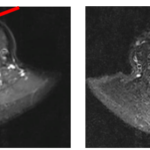

Ca lâm sàng: Điều trị thành công bệnh nhân ung thư tuyến giáp đã di căn xương cột sống sau 16 năm tại Trung tâm Y học hạt nhân và Ung bướu

GS.TS. Mai Trọng Khoa, PGS.TS. Phạm Cẩm Phương, Ths Lê Quang Hiển, BS. Vũ Thị Huyền Trung tâm Y học hạt...